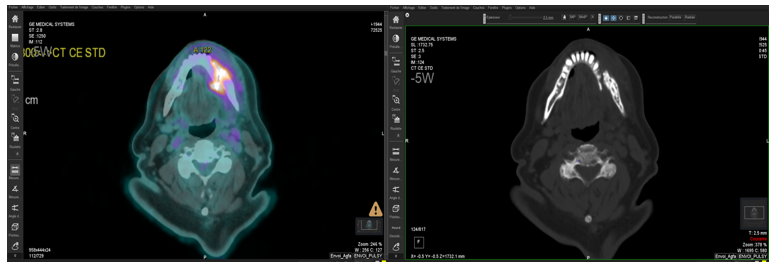

Our patient is an 80-year-old man, married, and the father of one son who died in a road traffic accident. He has a history of hypertension and diabetes, both well controlled with medical treatment. He was admitted to our department for the management of a solitary plasmacytoma of the mandible. The disease appears to have started approximately three months prior to admission, with the onset of localized swelling and dental mobility, prompting him to consult his dentist. A panoramic dental X-ray and a CT scan of the facial bones were performed, revealing a semi-recent left parasymphyseal mandibular fracture with significant mandibular osteocondensation and an associated anterior periosteal reaction. These findings were highly suggestive of chronic osteomyelitis complicating the aforementioned fracture. There was also evidence of phlegmon involving the soft tissues surrounding the left mandibular body in the area of the fracture, without any clearly organized collection.

Figure 1: Left mandibular osteolytic lesion on orthopantomogram in a patient with plasmacytoma.

As part of the staging workup, an FDG-PET scan confirmed that the mandibular plasmacytic lesion was solitary, with a few benign-appearing lymph nodes in the cervico-thoracic region. The case was discussed in a multidisciplinary hematology meeting, and given the patient's refusal of surgery, the decision was made to proceed with exclusive radiotherapy.

Figure 4: PET-CT scan slice showing hypermetabolism corresponding to the left mandibular fracture involvement, with a SUVmax of 8.6 compared to a hepatic reference of 3.6.